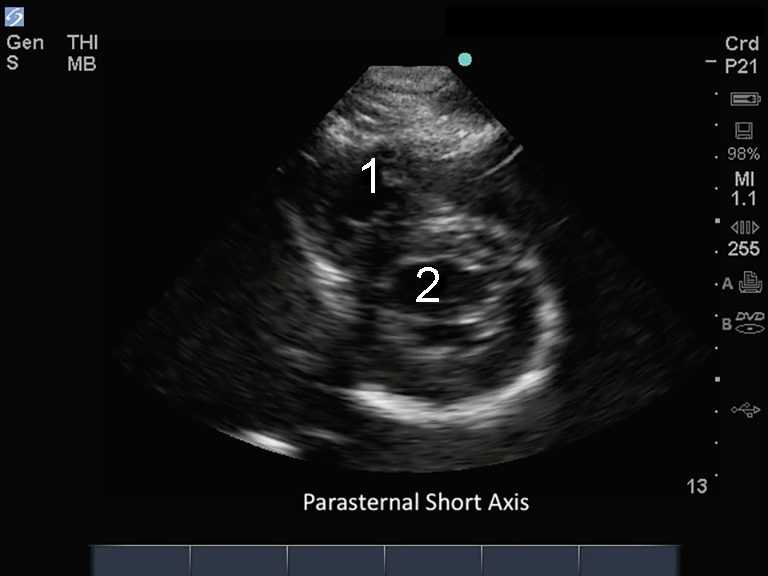

M-Turbo: 傍胸骨短軸

右心室 (RV)

左心室(LV)